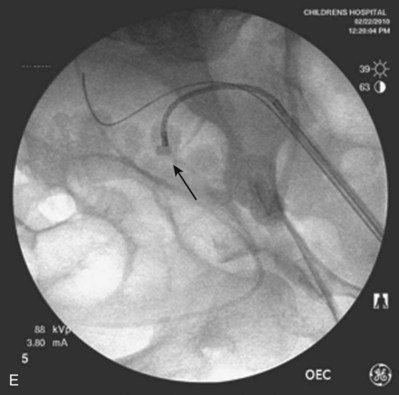

Figure 135–5 Altered anatomy in a 17-year-old male spina bifida patient who underwent a high thoracic myelomeningocele closure at birth (A). A computed tomography (CT) scan performed for a gross hematuria workup revealed bilateral nephrolithiasis in pelvic kidneys (B). The right retrograde pyelogram (C) demonstrated the lower pole stone (short arrow) and a torturous ureter almost taking a perpendicular course (long arrow). Placement of a ureteral access sheath (D) straightened the ureter (white arrow). This allowed easier access to address the stone (short arrow in D) with a flexible ureteroscope (E).